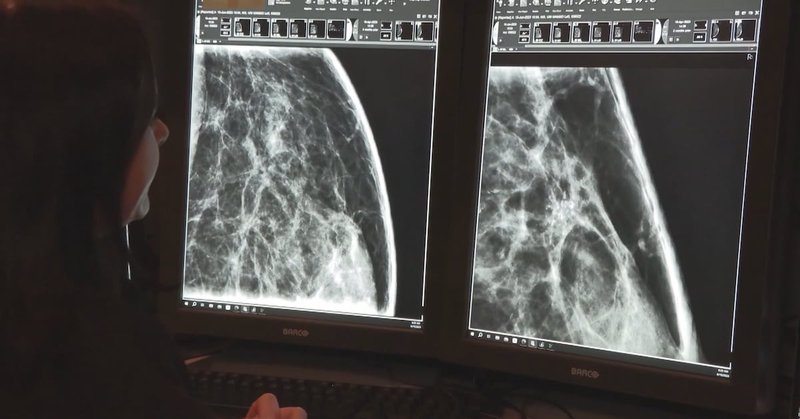

BC’s largest health authority is spending millions on 40+ AI programs — and they won’t discuss them Why? I don’t think the public is ever happy w a lack of accountability, but when it’s so hard to see a dr the secrecy around $ and priorities is…not good https://t.co/YaPHVC0tIm

ctvnews.ca

Fraser Health is aggressively pursuing artificial intelligence programs with at least 40 initiatives underway, but the health authority refuses to make any officials available to discuss whether the...

For many, the uses & potential benefits of AI are still theoretical, but for a lot of BC's healthcare providers it's already part of their daily medical practice It's also going to be a foundational element at @SFU's new medical school Part 1 in a series: https://t.co/6nMylawwcb

ctvnews.ca

British Columbia’s medical community is buzzing with enthusiasm and ideas, personal anecdotes and concerns, as the adoption of artificial intelligence becomes increasingly mainstream – and valuable.